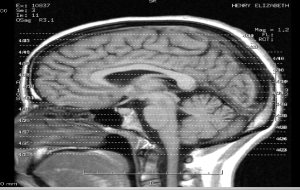

my brains - let me show you themA few days ago I received a request from a reader (Thanks Paulo Zan) for information about magnetic resonance. The request did not specify more than that so I took the liberty of deciding that perhaps the request was due to coming across the term before and as such it is quite possible that a lot of us would have heard of magnetic resonance in the context of MRI scans.

Well, an MRI scan stands for “Magnetic Resonance Imaging” Scan and it is a widely-used technique to obtain images of the brain. The full name of the imaging technique is actually nuclear magnetic resonance imaging but it seems that the first word in that mouthful is sometimes avoided as it may have negative connotations for some. Other names include MRT or magnetic resonance tomography. MRI scanners use strong magnetic fields and radio waves to form images of the body.